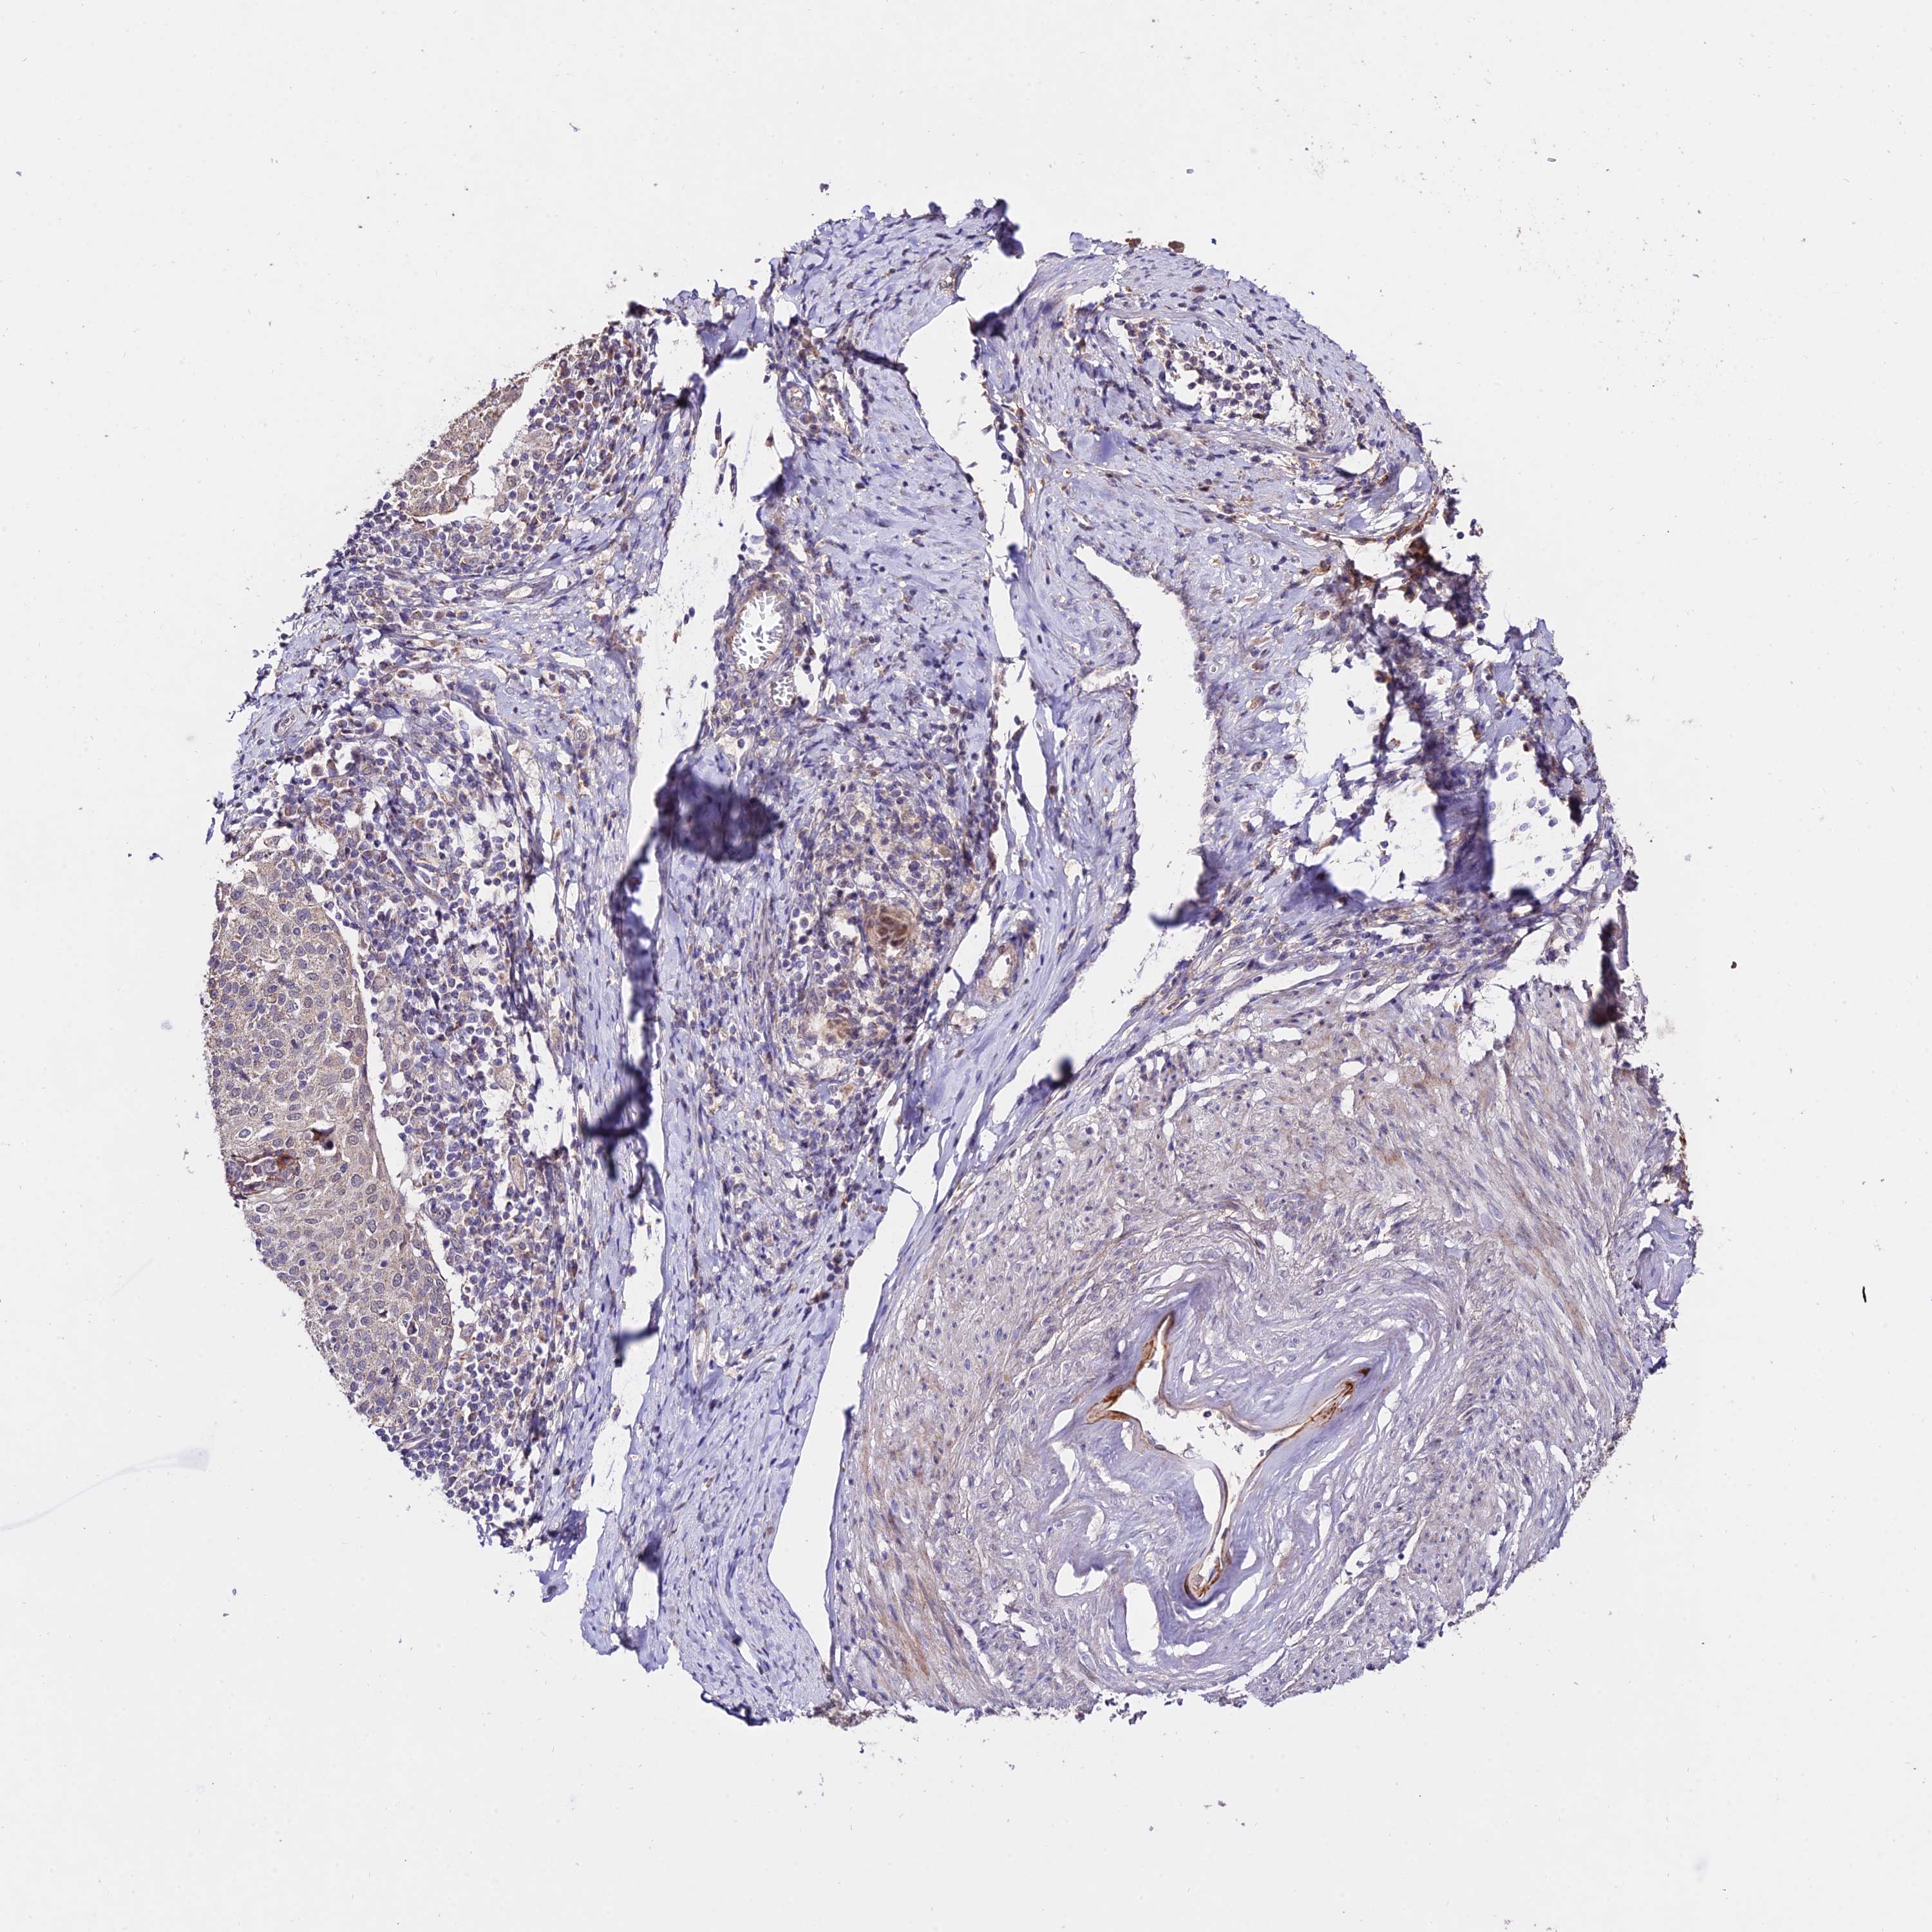

CERVICAL CANCER - Protein expressioni

A mouse-over function shows sample information and annotation data. Click on an image to view it in a full screen mode. Samples can be filtered based on level of antibody staining by selecting one or several of the following categories: high, medium, low and not detected. The assay and annotation is described here.

Note that samples used for immunohistochemistry by the Human Protein Atlas do not correspond to samples in the TCGA dataset.

Antibody stainingi

Antibody staining in the annotated cell types in the current human tissue is reported as not detected, low, medium, or high, based on conventional immunohistochemistry profiling in selected tissues. This score is based on the combination of the staining intensity and fraction of stained cells.

Each image is clickable and will lead to virtual microscopy that enables deeper exploration of all samples and also displays staining intensity scores, fraction scores and subcellular localization as well as patient and tissue information for each sample.

Antibody HPA042994

Staining

High

Medium

Low

Not detected

Intensity

Strong

Moderate

Weak

Negative

Quantity

>75%

75%-25%

<25%

None

Location

Nuclear

Cytoplasmic/membranous

Cytoplasmic/membranous,nuclear

Squamous cell carcinoma, NOS

Adenocarcinoma, NOS